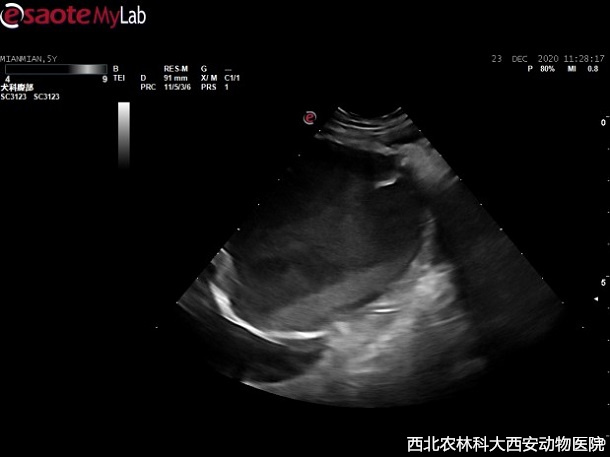

輔助檢查:主人自帶腹部平片顯示前列腺增大,膀胱前列腺區(qū)域有一明顯占位待查。超聲提示:前列腺增生且伴有囊腫,緊鄰前列腺和膀胱可見無回聲異常囊性占位,與周圍組織有聯(lián)系,疑似粘連見(圖1)。

圖一